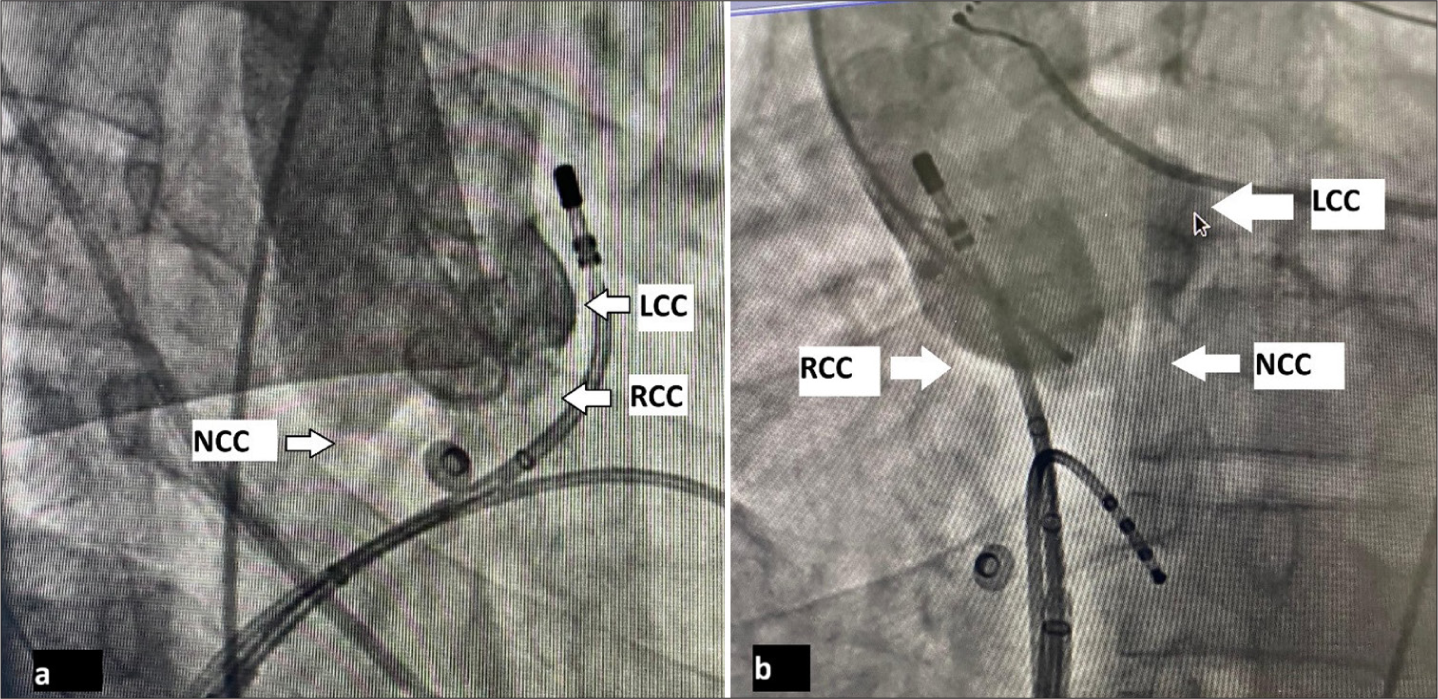

Clinical examination and baseline laboratory parameters were normal. He was taken for electrophysiological study + 3-D mapping with CARTO Biosense Webster. An activation and pace map of both RVOT and left ventricular outflow tract (LVOT) was created [Figures 2ab and 3]. VPCs were localized to the posterior RVOT. To demonstrate the proximity of RCC and posterior RVOT, an angiogram of the aortic root was done with a pigtail catheter positioned in the aortic root [Figure 4a and b]. Subsequently, three lesions were given with the Navistar thermocool ablation catheter in post RVOT with 30-watt power, each lesion for a duration of 40 s [Figure 5]. VPCs disappeared during the first lesion. The procedure was successful and uneventful. He was asymptomatic and had no VPC burden on 24-h Holter on follow-up at 2-, 6-, and 8-week post-procedure.

- (a) Aortogram in RAO 30°. (b) Aortogram in LAO 60°. (RCC: Right coronary cusp, LCC: Left coronary cusp, NCC: Non-coronary cusp.)